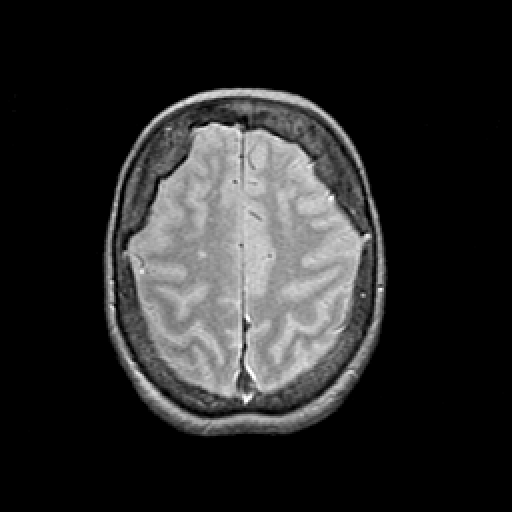

Proton density-weighted structural MR: Slice 41

Slice 41